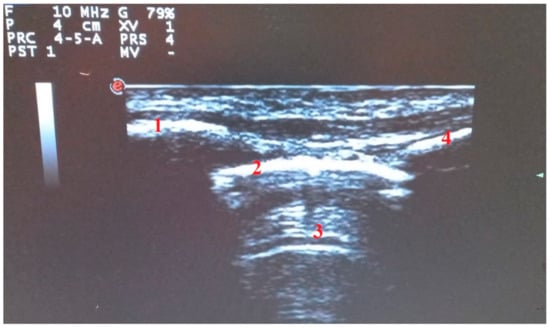

- Di Serafino, M.; Notaro, M.; Rea, G.; Iacobellis, F.; Paoli, V.D.; Acampora, C.; Ianniello, S.; Brunese, L.; Romano, L.; Vallone, G. The lung ultrasound: Facts or artifacts? In the era of COVID-19 outbreak. Radiol. Med. 2020, 125, 738–753. [Google Scholar] [CrossRef] [PubMed]